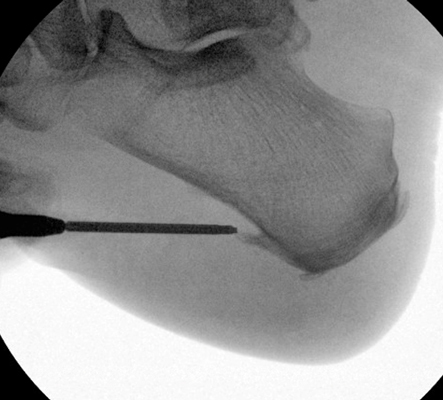

Your doctor may order imaging studies such as X-ray to confirm the diagnosis.